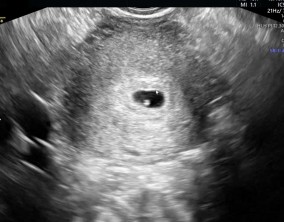

임신 수치 16, 9주차 기적의 기록